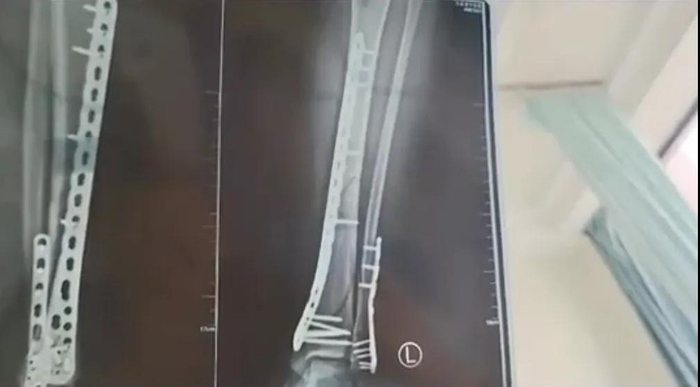

近日,甘肃兰州的武女士发文表示,不久前她穿着7厘米厚的增高洞洞鞋下楼,结果不慎崴脚摔倒,造成左腿粉碎性骨折。

武女士表示,目前她已做完手术在家休养,完全康复可能需要3个月。她提醒大家,穿增高鞋时一定注意安全。